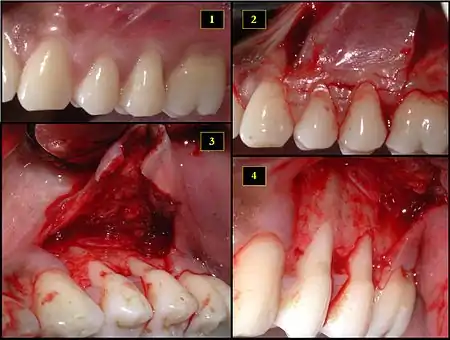

1. Recipient site exhibits gingival recession on both premolars and first molar (molar recession is not an esthetic issue and will not be treated)

2. Incisions prior to flap reflection

3. Full thickness flap elevated

4. Another viewpoint of the flapped recipient site

1. Ipsilateral palatal mucosa serving as the donor site

2. The retrieved connective tissue, approximately 25 × 6 mm in dimension

3. Connective tissue placed at recipient site

4. Recipient site flap coronally advanced and sutured to entirely cover the graft